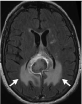

MRI of the brain was performed with and without contrast and showed multiple hyper-intense lesions involving the basal ganglion, thalamus, midbrain, pons, temporal lobe, occipital lobe, and enhancing corpus callosal lesions. There was no evidence of edema, necrosis, or ring enhancement, as shown in Figure 1. Lesions were found to cross the midline via the corpus callosum.

Figure 1: MRI of the brain a) Axial FLAIR showing corpus callosal lesion; b) Axial DWI of corpus callosal lesion; c) Axial FLAIR showing midbrain and temporal lobe lesion; d) Axial DWI of midbrain and temporal lobe lesion; e) Axial FLAIR showing thalamus and basal ganglion lesion; f) Axial T1 contrast showing enhancement of corpus callosal lesion; g) Coronal T1 contrast showing enhancement of corpus callosal lesion. View Figure 1